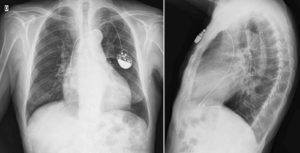

Bicamerales: es la elección más común y preserva la conducción auriculoventricular poniendo dos catéteres en las cámaras del corazón (aurícula derecha y ventrículo derecho). Son usados en los pacientes en los que se puede mantener el ritmo sinusal.

Mediante una técnica de punción se realiza el acceso al sistema venoso y la colocación del catéter empleando los rayos X. Se realiza la fijación del marcapasos al músculo y se cierran los planos musculares hasta el cierre de la piel.

Se realiza en un área de cuidados coronarios y requiere la observación continua del ritmo cardíaco y control con radiografía de tórax.

El primer control debe de realizarse a los 15 días con una radiografía de tórax y un electrocardiograma . El